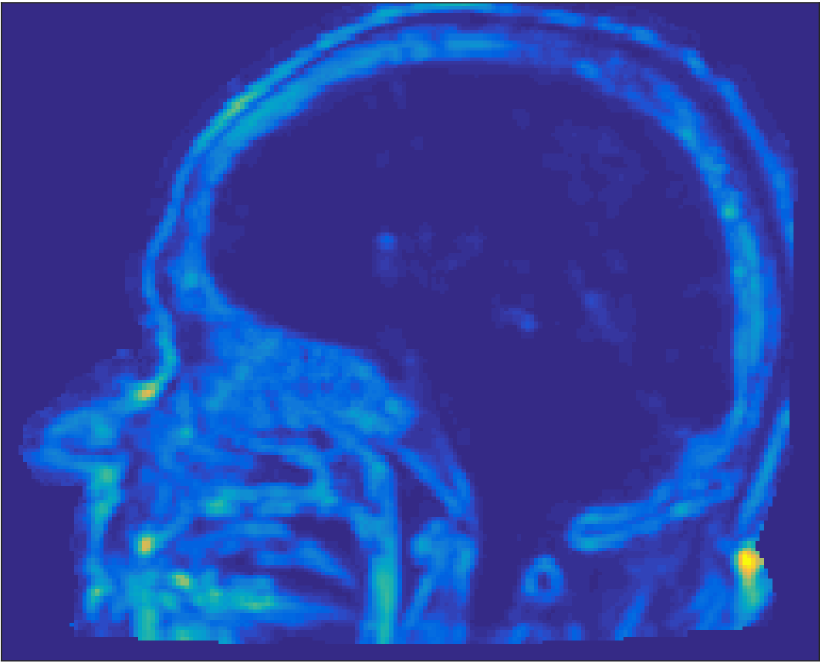

All MR images were acquired with a 1.5 T Siemens Espree scanner. The UTE images were reconstructed to 192×192×192192192192192\times 192\times 192 voxel bitmapped images with an isotropic resolution and a voxel size of 1.33 mm. The UTE sequences sampled the k-space radially with 30 000 radial spokes. CT images were acquired with a tube voltage of between 120 kV and 130 kV on either a GE Lightspeed Plus, Siemens Emotion 6 or GE Discovery 690. The in-plane pixel size varied between 0.48 mm to 1.36 mm and the slice thickness between 2.5 mm and 3.75 mm. Images of the same patient were co-registered and resampled to achieve voxel-wise correspondence between all five modes. A binary mask excluding most of the air surrounding the head was computed from the images and used to remove unnecessary data. Furthermore, to reduce the execution time of the parameter estimation phase, only 11 slices in the middle of the head of each patient was used during the parameter estimation phase, but all slices were used during the prediction phase (s-CT generation). Additional details concerning the data can be found in Johansson et al. [16]. Data from one slice of a patient is shown in Figure 3.

Refer to caption

(a) Binary mask

(b) CT

(c) First echo, 10superscript1010^{\circ}

(d) Second echo, 10superscript1010^{\circ}

(e) First echo, 30superscript3030^{\circ}

(f) Second echo, 30superscript3030^{\circ}

Figure 3: Binary data mask (panel a), CT image (panel b), The four MRI UTE sequences (panels c-f).